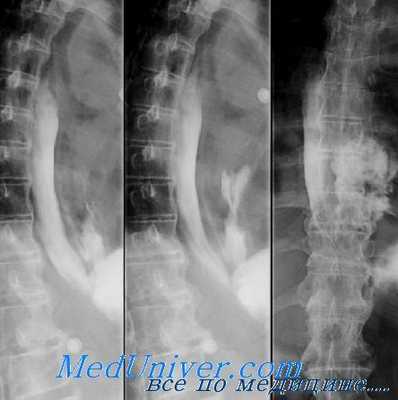

При обзорной рентгенографии грудной клетки и брюшной полости выявляется скопление газа в средостении (пневмомедиастинум) и параэзофагеальном пространстве, гидропневмоторакс. Проведение рентгенографии пищевода с водорастворимым контрастом позволяет увидеть выход вещества за пределы эзофагеальной стенки и уточнить место разрыва пищевода. В сомнительных случаях выполняется фарингоскопия, эзофагоскопия, медиастиноскопия.

При подозрении на перфорацию пищевода в первую очередь необходимо провести обзорную рентгенографию органов грудной клетки и брюшной полости: они выявят жидкость и воздух в плевральных полостях и брюшной полости, эмфизематозность клетчатки средостения и шеи. Для выявления локализации дефекта в пищевод вводится водорастворимый контраст, и производятся снимки в положениях на спине, на животе, на боку. Миграция контрастного вещества в околопищеводную клетчатку позволит определить локализацию и размеры перфорации пищевода.